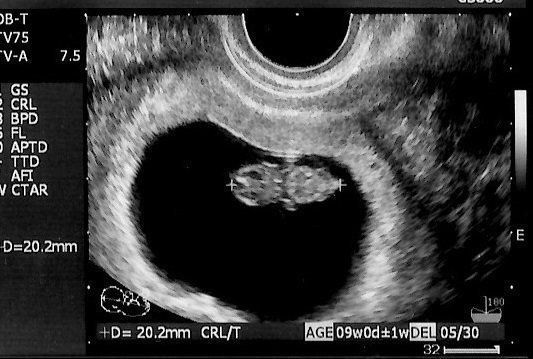

妊娠9週目のエコー写真 胎児の姿が見えてきた!

エコー画像で頭と胴体が分かれた人間らしい姿を見て、いよいよ妊娠したという実感がわいてきました。それと同時に、このまま無事に育ってくれるのだろうかという不安で毎日祈るような気持ちでいました。いまだにこの画像を見るたびに、この時の不安でたまらなかった自分の気持ち、そして生命の神秘を目の当たりにしたときの厳粛な気持ちを思い出し、胸がいっぱいになります。